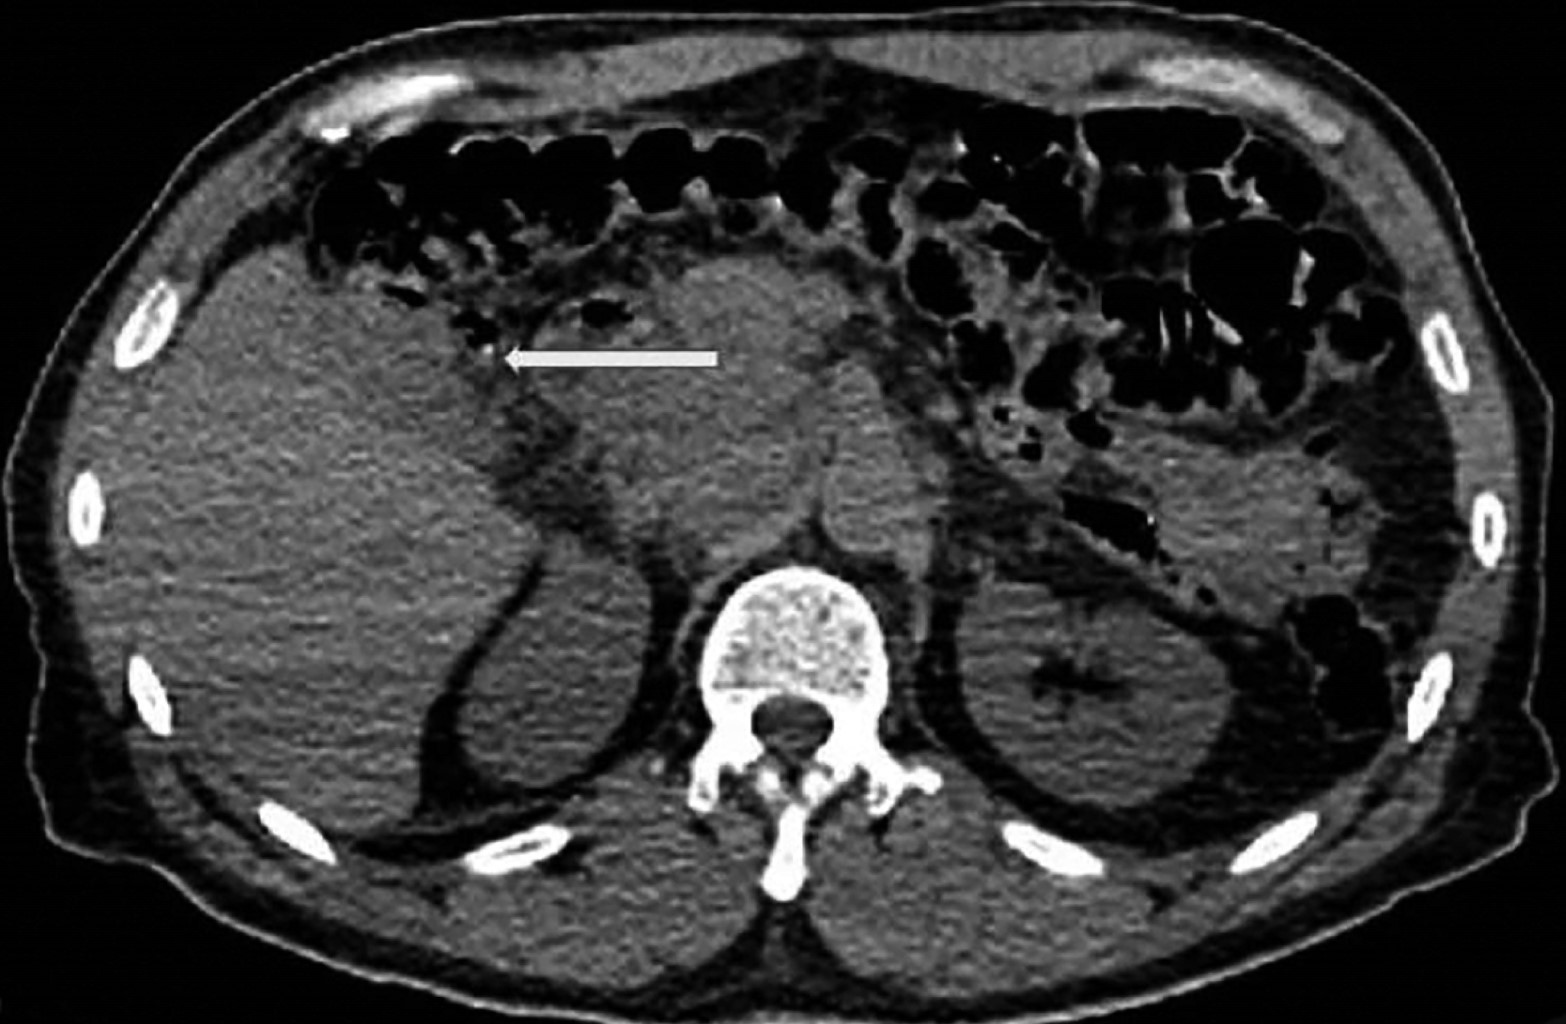

A la exploración física, el paciente se encontró en buenas condiciones generales, se propuso segmentectomía V-IVB; sin embargo, por antecedente de infarto agudo de miocardio se sometió a quimioembolización transarterial (TACE), después se solicitó una tomografía axial computarizada (TAC) con presencia de lesión hipodensa mal definida en segmento V (Figuras 1 y 2), por lo que es sometido a colecistectomía y resección de segmento V y VI, con reporte de carcinoma hepatocelular moderadamente diferenciado con patrón trabecular y sólido focal, sin células neoplásicas en el lecho quirúrgico. Al presentar metástasis peritoneales dentro de su seguimiento, se decidió su adyuvancia con quimioterapia, el paciente mostró adecuada respuesta al disminuir las metástasis peritoneales 10 años después. En la actualidad, el paciente sigue vivo en adecuadas condiciones clínicas.

Figura 2